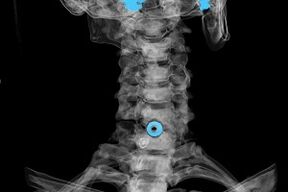

Ախտորոշում

Ախտորոշումը սահմանվում է բնորոշ ախտանիշների հիման վրա, ինչպես նաև օգտագործելով.

- ռենտգենյան ճառագայթներ. Մեթոդն անարդյունավետ է հատկապես օստեոխոնդրոզի զարգացման վերջին փուլերում։

- Արգանդի վզիկի ողնաշարի MRI (մագնիսական ռեզոնանսային պատկերացում): Մեթոդ, որը թույլ է տալիս տեսնել ոսկրային կառուցվածքները, միջողնաշարային սկավառակների ճողվածքը, դրանց չափը և զարգացման ուղղությունը։

- Համակարգչային տոմոգրաֆիա. Ավելի քիչ արդյունավետ լուծում, քան MRI-ն, քանի որ ճողվածքների առկայությունը և չափը դժվար է որոշել: